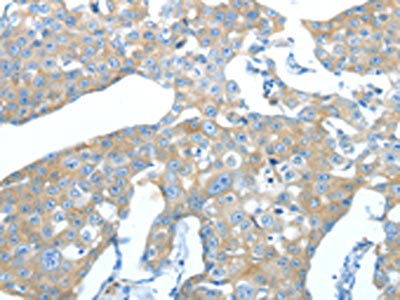

• The image on the left is immunohistochemistry of paraffin-embedded Human liver cancer tissue using CSB-PA068489(AMPH Antibody) at dilution 1/25, on the right is treated with fusion protein. (Original magnification: ×200)

• The image on the left is immunohistochemistry of paraffin-embedded Human breast cancer tissue using CSB-PA068489(AMPH Antibody) at dilution 1/25, on the right is treated with fusion protein. (Original magnification: ×200)